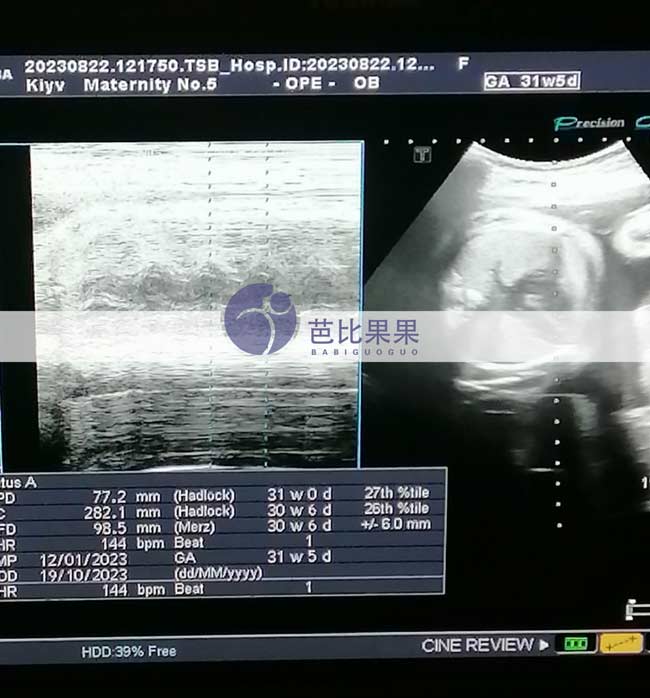

Z先生的乌克兰试管妈妈按时来做孕31周+的B超

Z先生家的乌克兰试管妈妈按时来做了孕31周+的B超,胎儿已经越来越大了,期待TA的到来